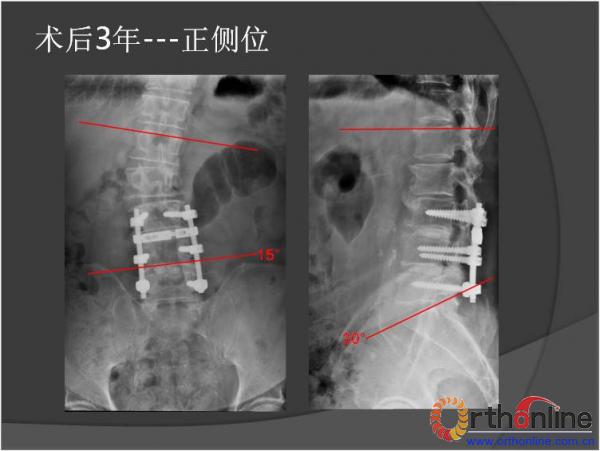

北京军区总医院骨科李放教授报告了一例腰椎管狭窄脊柱融合术后、退变侧凸加重并出现邻近节段退变病、而后进行翻修的病例。患者男性,64岁,2009年因腰椎管狭窄症行椎板减压,L3-4、L4-5PLIF手术,术后3年间疗效满意,后由轻度扭伤后再度出现腰痛及下肢疼痛,经检查后发现L2-3间盘退变、L1-2间盘突出并出现退变性腰椎侧凸,于2013年2月行翻修手术后痊愈。